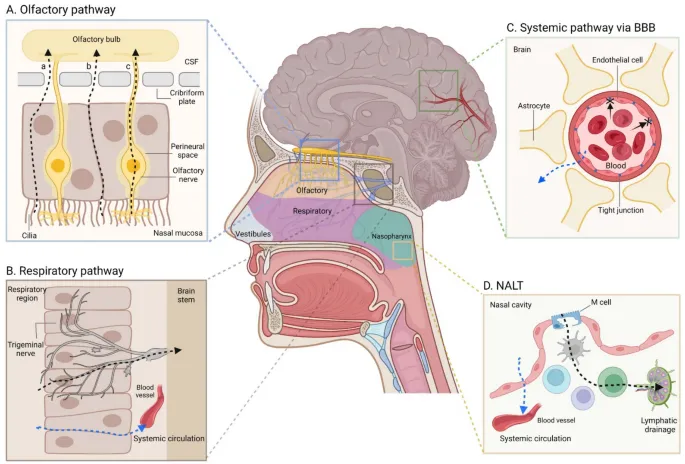

化疗发展于 20 世纪 40 年代,是癌症患者的主要治疗手段。然而,由于血脑屏障限制了许多药物进入脑组织,脑癌患者面临着独特的挑战。因此,某些化疗药物被设计成能穿过血脑屏障,靶向作用于脑部癌细胞。

目前正在开发新的给药方式,例如鼻腔给药:

化疗通常与手术和放疗等其他治疗方法结合使用,以最大限度地提高抗癌效果。但许多问题也随之而来: